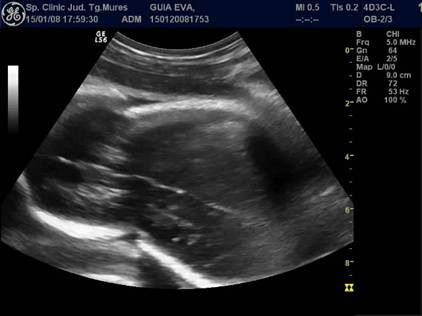

Fig. nr. 239 Aparitia de bule in cavitatile toracica si abdominala ( sageti ), dupa maceratie la fatul mort intrauterin , la 34 sapt.